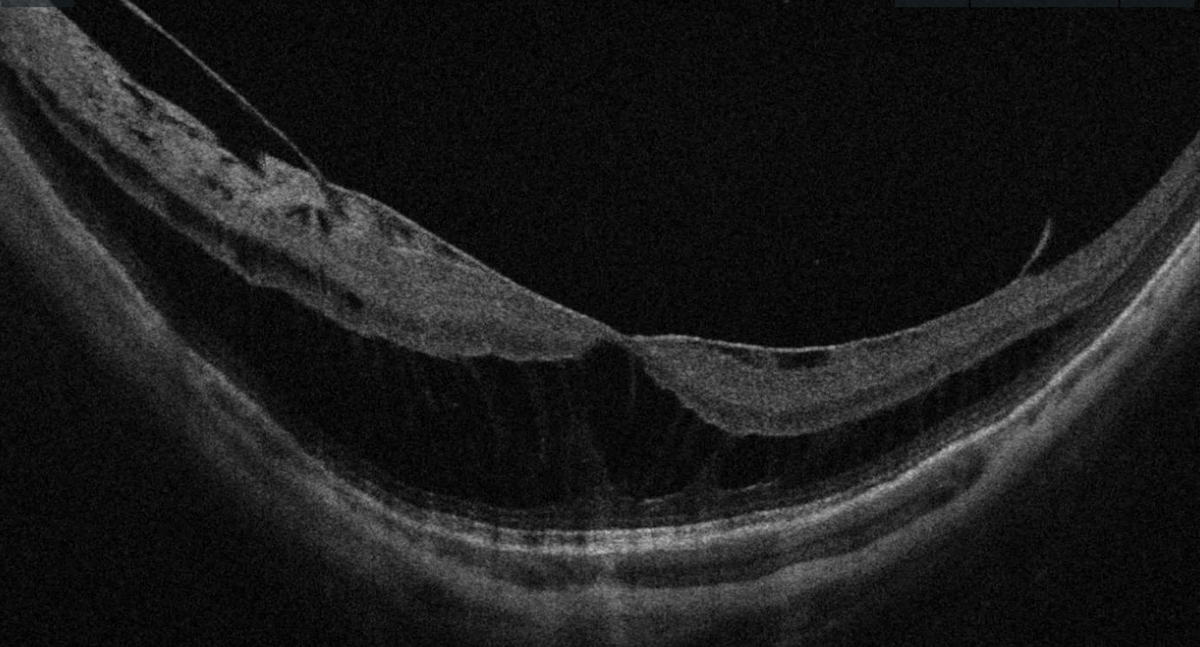

Fovéoschisis myopique

Clivage des couches rétiniennes au niveau de la fovéa, visible en OCT sous forme de séparation des couches internes et externes. Touche 9 à 34 % des yeux avec staphylome. L'évolution peut être lente et la vision relativement préservée initialement, mais le risque de progression vers un décollement fovéolaire ou un trou maculaire justifie une surveillance rapprochée.

OCT maculaire montrant un fovéoschisis du myope fort — clivage des couches rétiniennes internes et externes au niveau fovéolaire

OCT Cirrus — Fovéoschisis du myope fort : clivage des couches rétiniennes au niveau fovéolaire (IPO Paris)